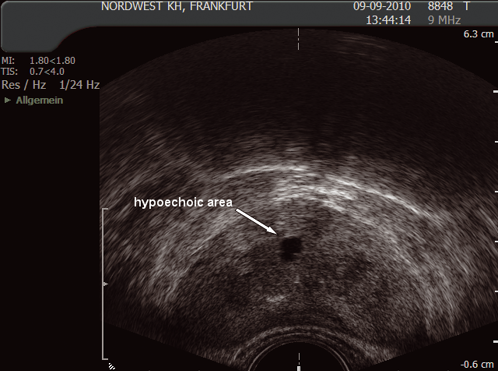

The sonographic appearance of the prostate is not specific but there are three ultrasonic findings that may be described as isoechoic (same echogenicity as surrounding tissue), hyperechoic (brighter) or hypoechoic (darker). (Figs. 10 and 11)

Fig. 11. Hyperechoic areas

(Courtesy: S. Hieronymi)

Ultrasonic findings:

- isoechoic area could be normal tissue or tumour

- hypoechoic area could be cyst, abscess or tumour

- hyperechoic area could be calcification or tumour

Although these findings are interesting, they should not have any impact on the biopsy procedure or cause additional complications.